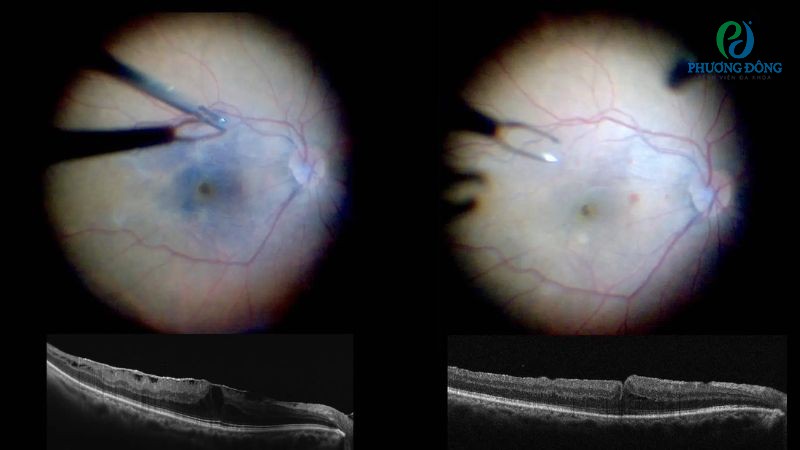

Can thiệp ngoại khoa

Cắt dịch kính và bóc tách màng tăng sinh dịch kính võng mạc thường được chỉ định với bệnh nhân tăng sinh dịch kính võng mạc. Tuy nhiên tùy thuộc vào vị trí định khu của màng, bác sĩ sẽ áp dụng phương pháp bóc phù hợp:

- Bóc màng trước võng mạc: Trường hợp bị dính ít chỉ cần bóc tách đơn giản để giải phóng võng mạc, nếu nhiều hơn cần cắt đoạn.

- Bóc, cắt những màng trước võng mạc: Đây là kỹ thuật ngoại khoa khó, phức tạp do phụ thuộc nhiều vào cấu trúc cũng như biến đổi cấu trúc võng mạc và mức độ dính giữa chúng.

- Bóc màng bằng đầu máy cắt dịch kính: Phương pháp này sử dụng đầu dao chuyên nghiệp, lướt nhẹ nhàng trên bề mặt võng mạc để vừa hút vừa cách. Tuy nhiên, kỹ thuật này không thể bóc những màng dày.

- Sử dụng kim, kéo: Bác sĩ dùng đồng thời hai dụng cụ để hút, cắt và tuyền theo kim những nút thần kinh đệm.